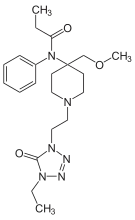

Anilidopiperidines

- 3-Allylfentanyl

- 3-Methylfentanyl

- 3-Methylthiofentanyl

- 4-Phenylfentanyl

- Alfentanil

- α-Methylacetylfentanyl

- α-Methylfentanyl

- α-Methylthiofentanyl

- Benzylfentanyl

- β-hydroxyfentanyl

- β-hydroxythiofentanyl

- β-Methylfentanyl

- Brifentanil

- Butyrfentanyl

- Carfentanil

- Fentanyl

- Lofentanil

- N-Methylcarfentanil

- Mirfentanil

- Ocfentanil

- Ohmefentanyl

- Parafluorofentanyl

- Phenaridine

- R-30490

- Remifentanil

- Sufentanil

- Thenylfentanyl

- Thiofentanyl

- Trefentanil

Structures